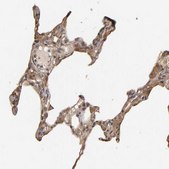

IHC

All Prestige Antibodies Powered by Atlas Antibodies are developed and validated by the Human Protein Atlas (HPA) project and as a result, are supported by the most extensive characterization in the industry.

The Human Protein Atlas project can be subdivided into three efforts: Human Tissue Atlas, Cancer Atlas, and Human Cell Atlas. The antibodies that have been generated in support of the Tissue and Cancer Atlas projects have been tested by immunohistochemistry against hundreds of normal and disease tissues and through the recent efforts of the Human Cell Atlas project, many have been characterized by immunofluorescence to map the human proteome not only at the tissue level but now at the subcellular level. These images and the collection of this vast data set can be viewed on the Human Protein Atlas (HPA) site by clicking on the Image Gallery link. We also provide Prestige Antibodies® protocols and other useful information.

• IHC tissue array of 44 normal human tissues and 20 of the most common cancer type tissues.